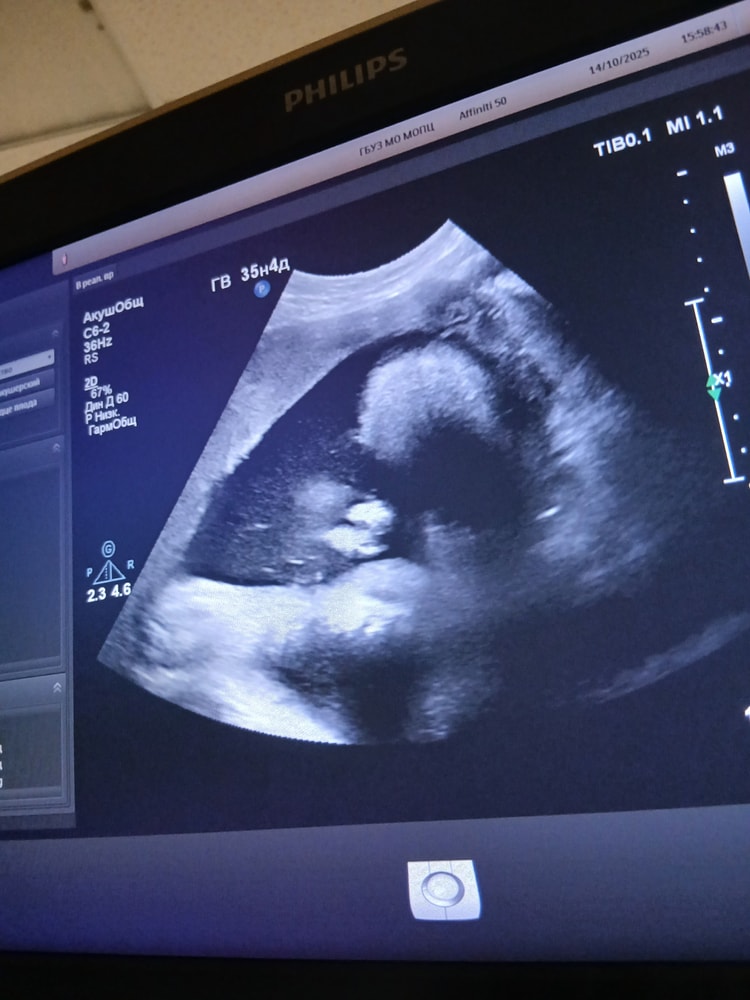

Младшенькая Виктория 14.10.25(35,0)

УЗИ, КТГ, доплерХодила на контрольное узи,многоводие таки осталось ИАЖ 250мм,ожидаемо если честно,во все беременности оно было,удивительно, что в этот раз оно только в 3 триместре появилось, а не как обычно во втором),по весу ставят 2865г +- 427г,самый маленький гномик из всех,может испытаю удачу и попробую родить не крупного ребёнка. Хотя и младшую уже прировняли к крупному плоду,хотя как по мне,это мало))

Ну и как же без фото))

Осторожно,одно из них 18+)))